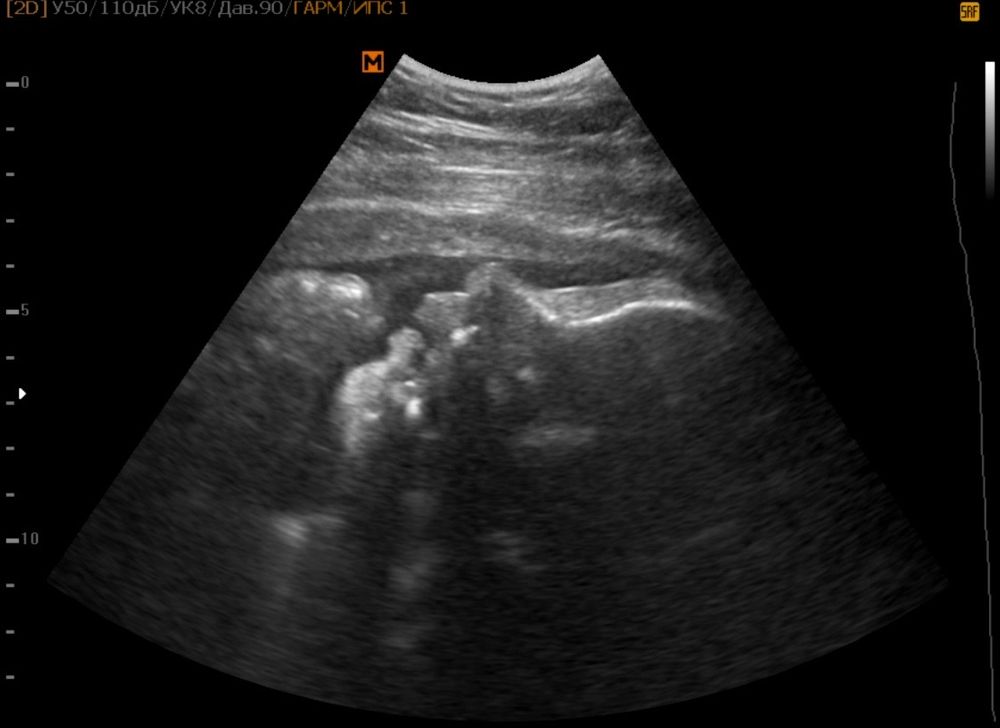

УЗИ, КТГ, доплерСходила сегодня на УЗИ, чтобы ещё раз глянуть на сына, узнать ушло ли обвитие и примерные размеры.

У нас все хорошо, одинарное обвитие так и осталось.

По узи срок ставят 35.1, чуть больше, чем по месячным.